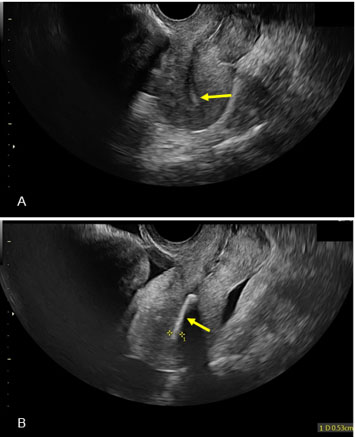

Figure 2: panel of two images obtained during ultrasound that identifies an echogenic substance within the uterine cavity. The echogenic substance is only seen in one view. (A) Transvaginal ultrasound showing 5.3 mm echogenic structure within the uterine canal. Note the absence of echogenicity in this view. (B) Note the presence of echogenicity in this second view.

Due to age, lack of vaginal exam findings, and previous known fertility, the patient was trialed on an initial treatment plan of ovarian stimulation with letrozole followed by intrauterine insemination (IUI). At a follow-up follicle check ultrasound, the ultrasonographer noted a retroverted uterus with a pronounced linear echogenic area with distinct shadowing within the canal, measuring 5.3 mm with a solid lining (Figure 2). One ultrasound view obscured this area, and the uterus appeared empty, but another showed a clear view of echogenicity in the uterine cavity. Incidentally, the ultrasonographer also identified a 61×56 mm fibroid in the myometrium. The patient denied any history of intrauterine device (IUD) and given her history of two previous D&Cs, the ultrasonographer notified the physician of possible retained bone.

Most notably, this case represents the importance of thorough ultrasound imaging in workups for secondary infertility. Had this patient received an ultrasound as part of their initial screening, this fetal bone may have been identified earlier. Given the return-to-fertility nature of retained bones as historically described, this patient potentially could have avoided further hormonal stimulation or reproductive endocrinology testing with early identification of the bone. This case also emphasizes the importance of astute and thorough ultrasonography, as the image of the bone was obscured in one ultrasonic view and unidentifiable in other modalities of imaging, such as hysterosalpingogram, that were previously performed.